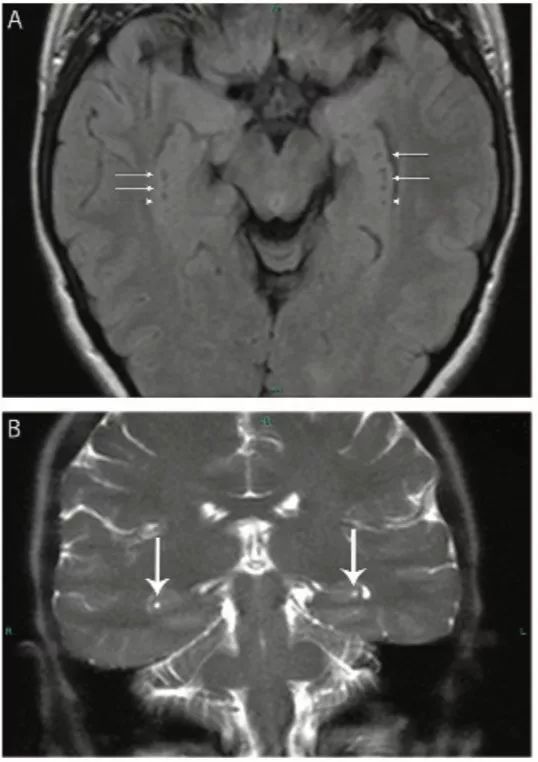

图6 海马沟残余囊肿

轴位FLAIR像(A)和冠状位T2WI像(B)显示双侧侧脑室内侧、颞叶小腔隙灶 (箭头)。